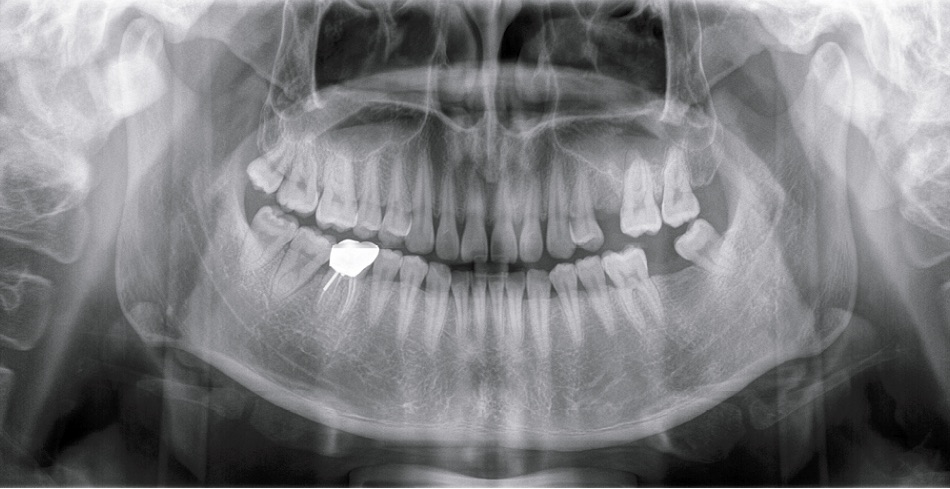

Aadva GX-100 2Dは、高品質なパノラマ、セファロX線撮影装置

です。エンド、ペリオなどの日常臨床や矯正治療などの様々な

歯科治療において正確で詳細な診断画像を提供します。

顎関節の観察

標準パノラマ撮影

顎骨直交パノラマ撮影

バイトウィングパノラマ撮影

分割パノラマ撮影

顎関節側方二重撮影

上顎洞撮影

正中矢状面測方スキャン